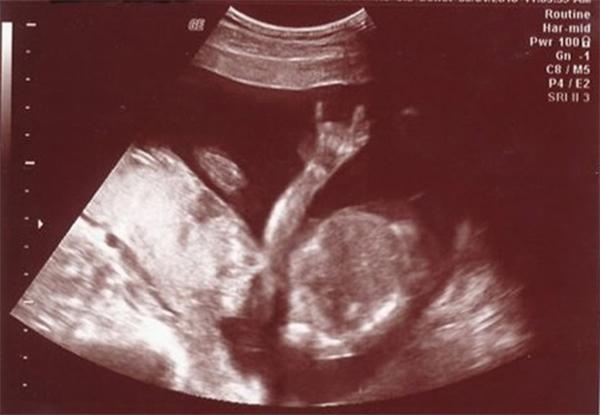

Thai nhi giơ biểu tượng Rock